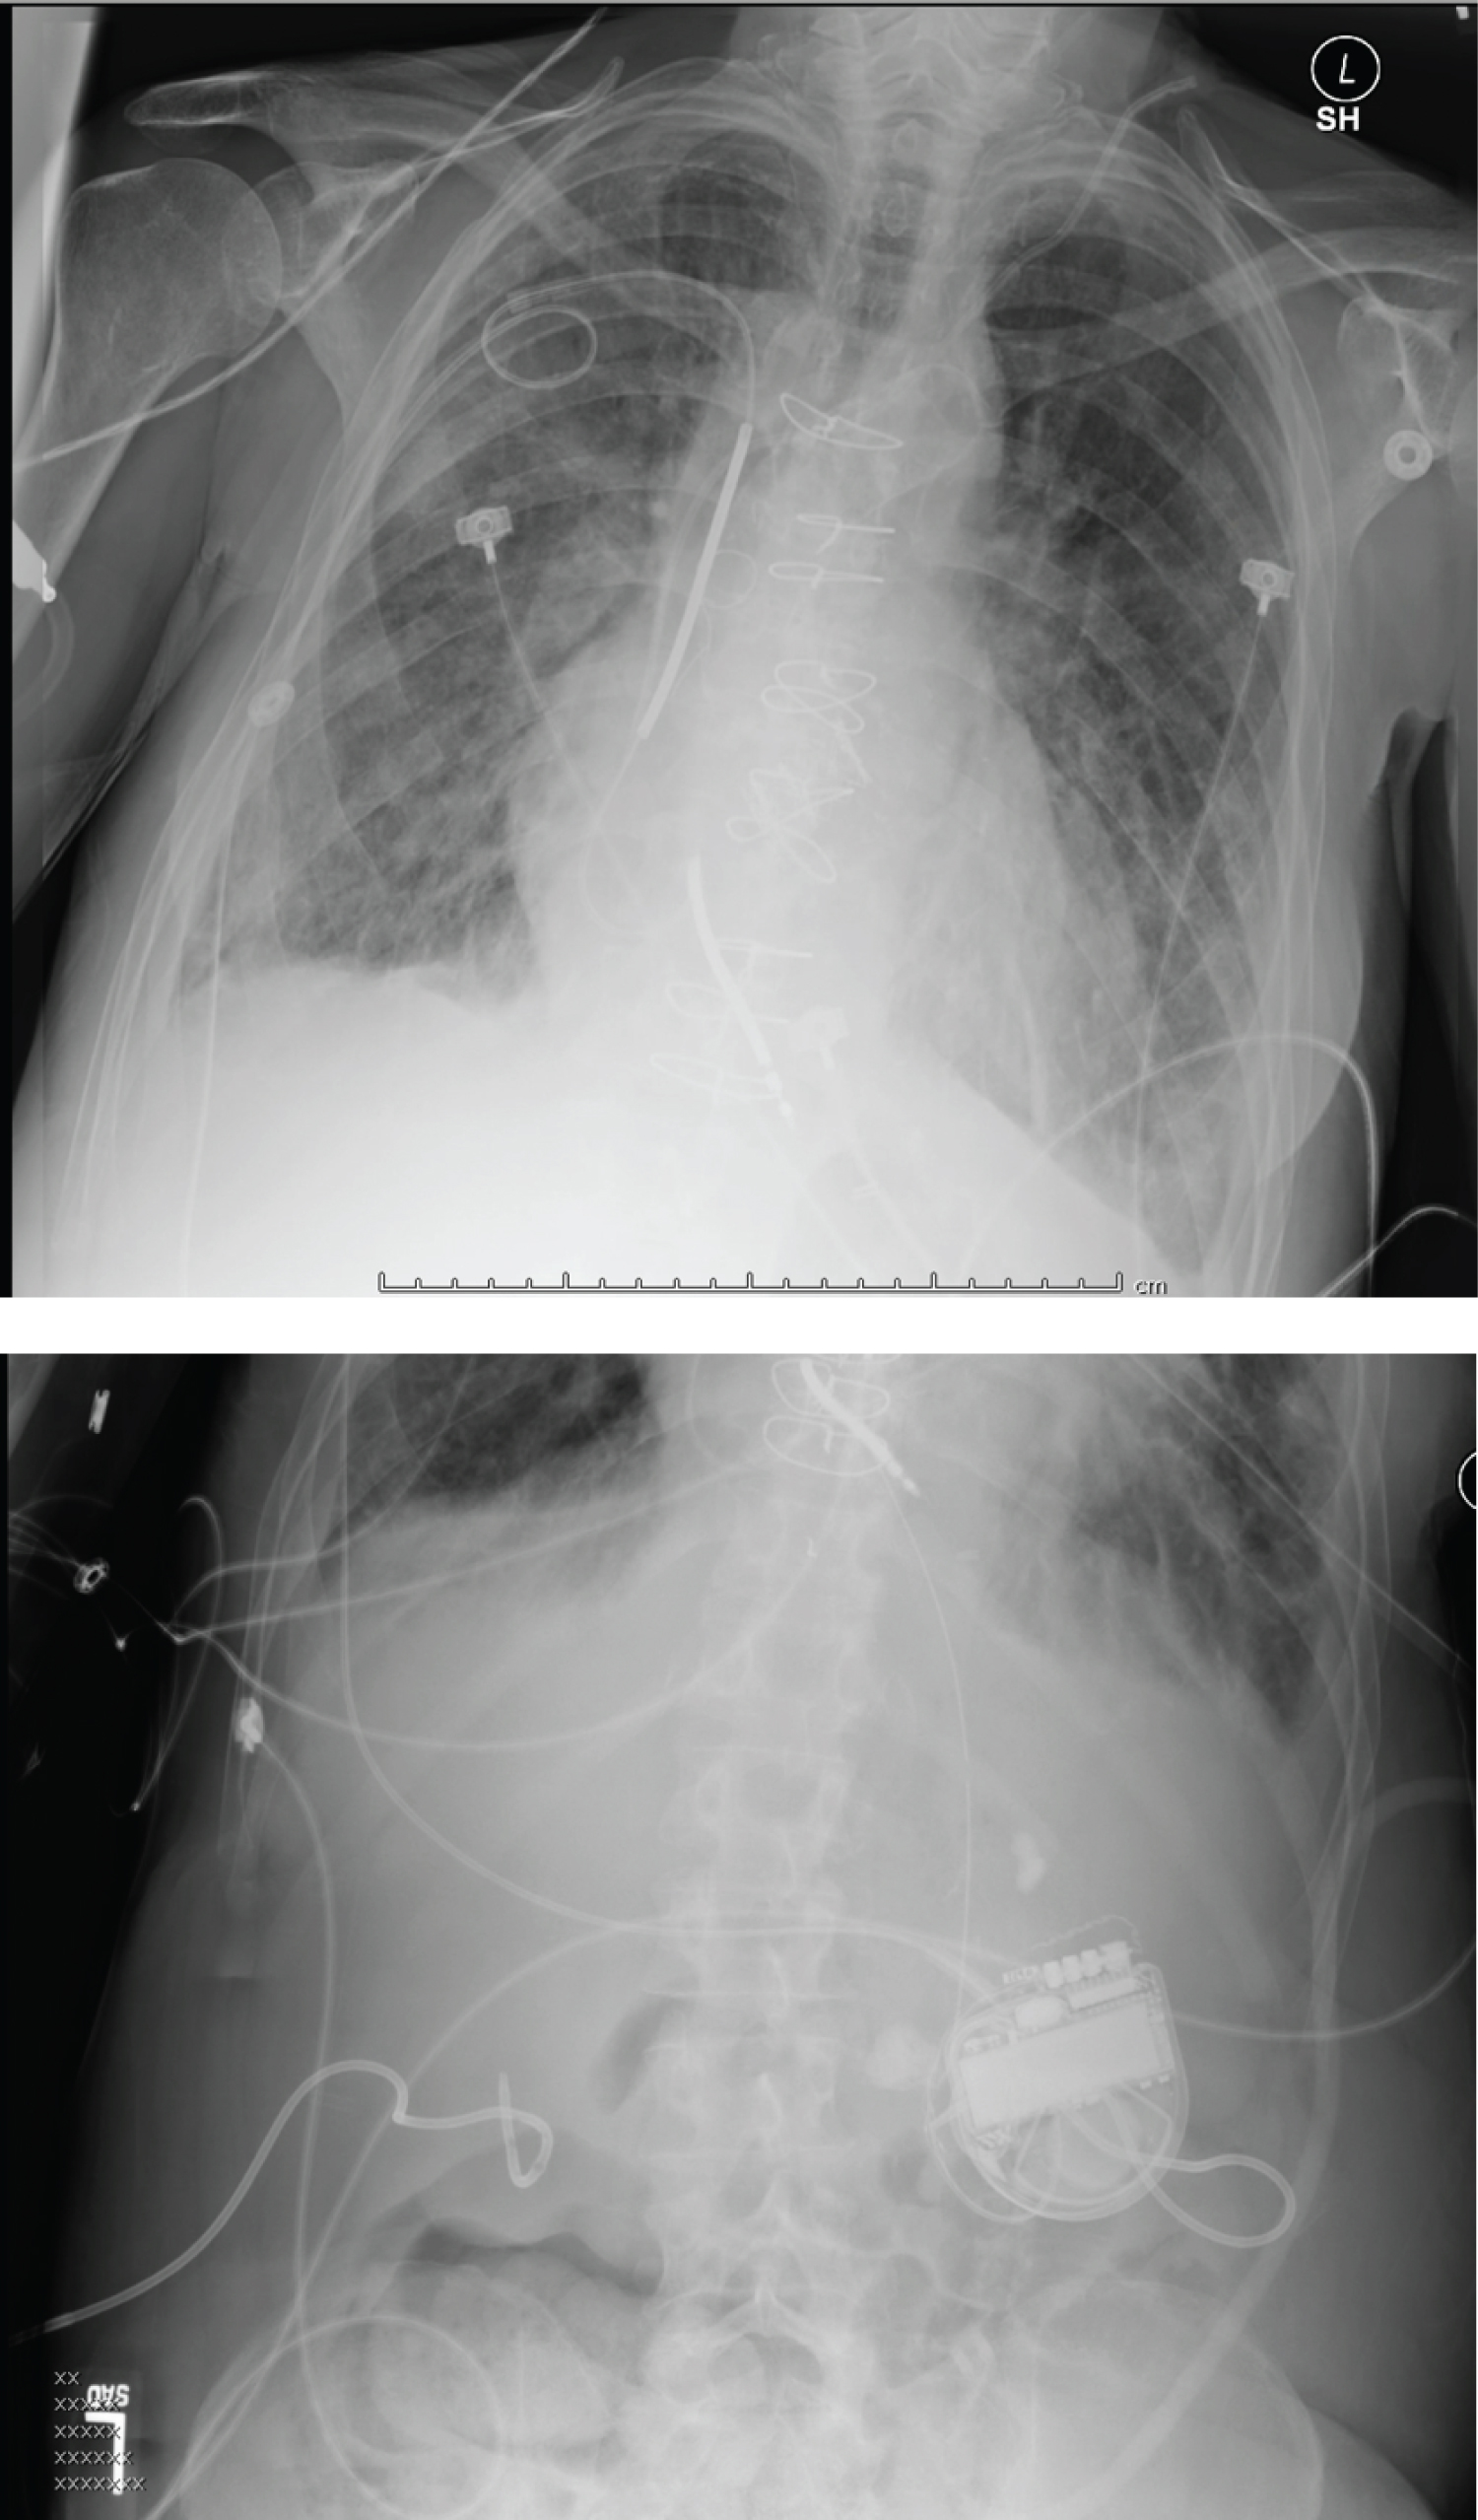

After a multidisciplinary case conference, it was recommended that patient should undergo aortic valve replacement. Patient underwent cardiac CT that showed near porcelain ascending aorta (Figure 2). It also revealed close proximity of LIMA to aorta and sternum. Treatment options for this patient at this time were either TAVR vs. apical aortic conduit placement. Patient underwent implantation of dual-chamber ICD for secondary prophylaxis of sudden cardiac death. During this procedure, atrial pacing was performed up to 180 bpm that showed one to one AV conduction with continued preexcitation. Patient was started on amiodarone to avoid recurrence of ventricular arrhythmias. Thereafter, he underwent TAVR with 26 mm sapient transcatheter aortic valve.

Figure 2: Cardiac CT demonstrating near porcelain aorta. View Figure 2

One year after his initial presentation, patient experienced erosion of ICD and underwent extraction of the device. He was discharged with a LifeVest and was brought after a month for implantation of another ICD with single right ventricular lead placement through right subclavian approach. The lead was tunneled through the chest wall and the defibrillator can was placed in the abdominal wall (Figure 3).

Figure 3: Right ventricular lead implanted through right subclavian approach with generator in abdominal cavity. View Figure 3